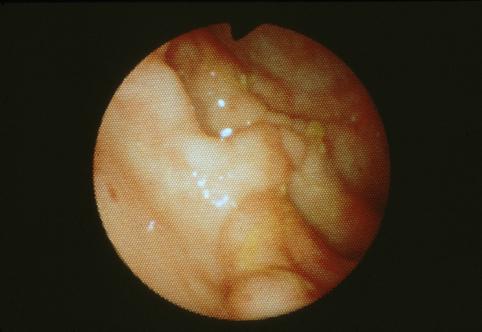

Caso de Enfermedad de Crohn del Recto

[Image-ID:2878]

Enfermedad Inflamatoria - Ulcerativa/Enfermedad de Chohn

parte(separada por órganos)

colon/recto

método de exámen

Endoscopia